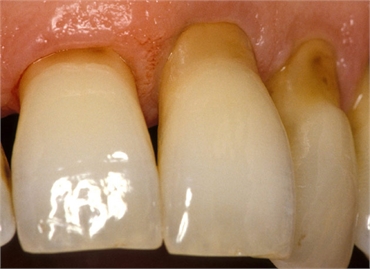

Teeth abrasion is a dental condition that involves the disintegration and loss of tooth structures usually caused by external forces such as toothbrushes and toothpicks. This condition starts by attacking the typically strong outer cover part of the tooth known as the enamel. Once past the enamel, tooth abrasion quickly destroys the much softer dentin and cementum tooth structures. This stretches onto the teeth roots, dismantling the roots and teeth gums holding your teeth. Since the enamel is usually tough to disintegrate, this condition usually starts from a weak-point enamel part of the tooth that is known as the cemento-enamel junction (CEJ). This junction is usually thinner than the other parts of the outer tooth cover thus allowing for quick erosion of its structure.

Tooth abrasion can also cause your gums to recede and therefore lose the much needed grip that is important for healthy teeth. Your facial look can be affected greatly since the premolars and canines turn out to be the most affected teeth by this dental condition. This might affect your confidence in smiling and speech. The condition is known to cause severe sensitivity or even pain if left untreated.